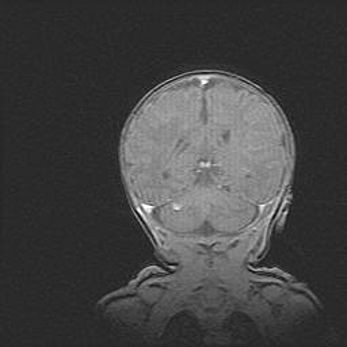

Сообщающаяся гидроцефалия. Кистозная энцефаломаляция головного мозга.

Возраст: 3 месяца 4 дня

Вес: 3100 г

Пол: женский

Окружность головы: 34 см

Срок гестации: 31 неделя

Кистозная энцефаломаляция головного мозга - одна из форм поражения головного мозга в детском возрасте. Характеризуется возникновением множественных и распространённых кист в коре, белом веществе и подкорковых образованиях головного мозга у плодов, новорождённых и детей раннего возраста. Развитие кистозной энцефаломаляции связано с внутриутробной асфиксией и гипотонией, родовой травмой, тромбозом синусов, пороками развития сосудов, инфекциями, сепсисом и другими причинами. Наиболее значимые инфекционные агенты: вирусы простого герпеса, цитомегалии, краснухи, токсоплазмы, энтеробактерии, золотистый стафилококк и другие.